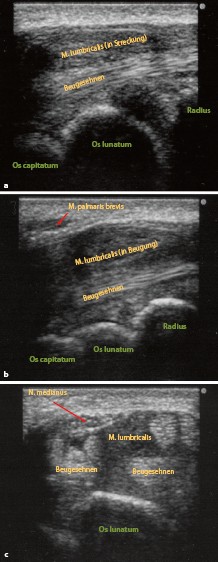

Sonografie Des Entzündlich Degenerativ Und Kompressiv - Sonografie Des Entzündlich Degenerativ Und Kompressiv